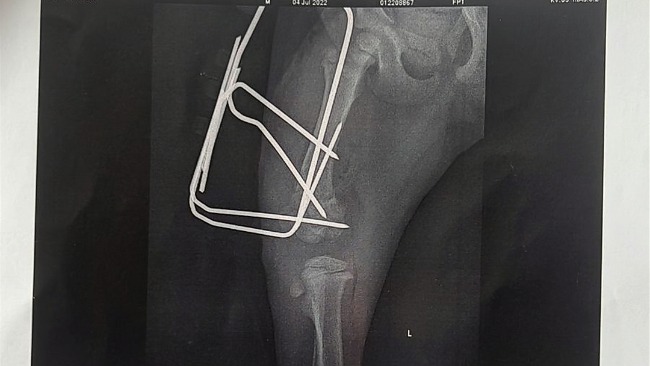

Kupili mnie ludzie, którzy chcieli bardzo mieć takiego przystojniaka jak ja, ale miałem wypadek, bawiąc się spadłem z tarasu na 2 piętrze, złamałem sobie nóżkę, moi właściciele zabrali mnie do kliniki, mam teraz taką metalową nóżkę i nie mogę się już bawić jak kiedyś. 😔 Ale najgorsze jest to że moi właściciele już mnie nie chcą 😥.

Pani z hotelu powiedziała mi, że jestem najsłodszym szczeniakiem jakiego widziała, i choć kuleję na jedną nóżkę, a z niej wystają jakieś metalowe druty, pokochała mnie i mówi że nie pozwoli bym trafił do jakiegoś "schroniska" - nie wiem, co to jest, ale to chyba nic dobrego. I tutaj potrzebne jest wsparcie, muszę nadal jeździć do kliniki, by wyleczyli moją nóżkę a to kosztuje trochę pieniędzy, a mojej nowej Pani na to nie stać, dlatego organizujemy zbiórkę, bym znów mógł się bawić jak kiedyś :)